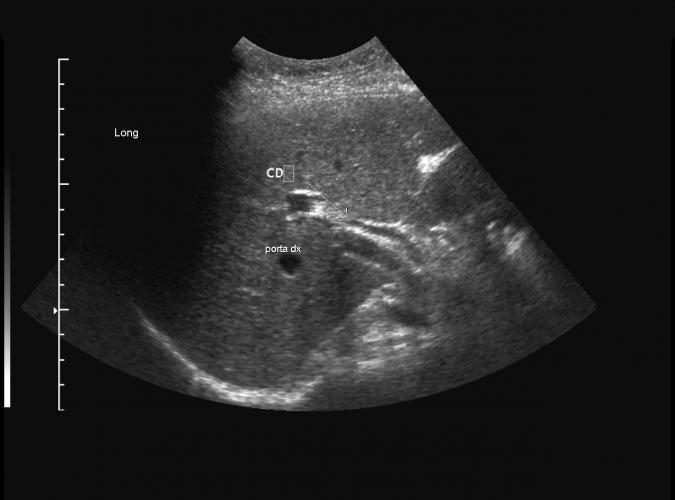

8a

av Catherine Olsson, sonograf

Post cholecystektomi patient. (a)Normalvid gallgång i leverhilus. Common duct (CD), ändå finns en choledochuskonkrement ..se bild 8b.